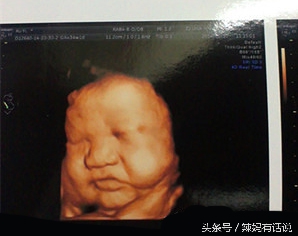

顺便还帮我拍了宝宝的脸,肉肉的!都说像他爸爸啊!